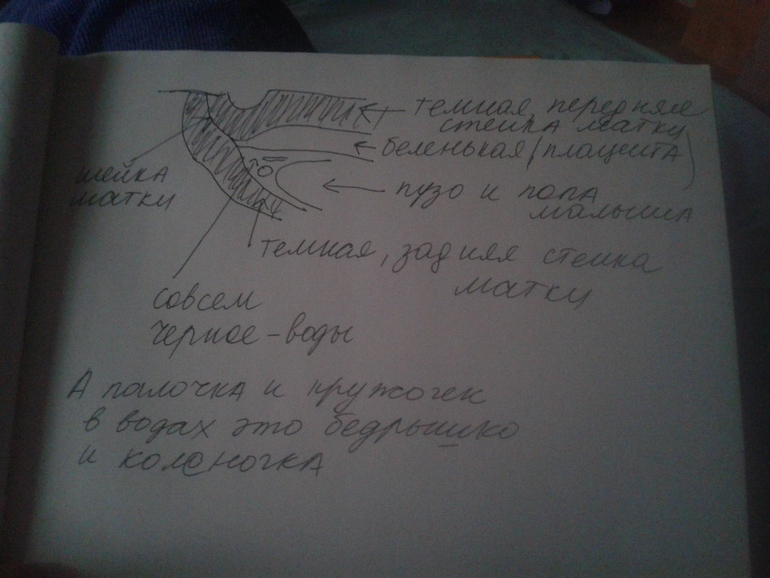

что вообще на фото?

Дала распечатку фото, но я понятия не имею что это вообще как на нем.